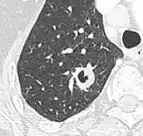

- A cavity has a wall thickness of more than 4 mm.[2]

Cavity

Two infectious diseases that are commonly associated with cavities of lung tissue are Mycobacterium tuberculosis and Klebsiella pneumoniae. The formation of cavities is due to tissue necrosis and creates an environment that allows the pathogen to expand in numbers and spread further.[10]

In the absence of infectious symptoms, a lung nodule with cavitation is a suspected lung cancer.[9]